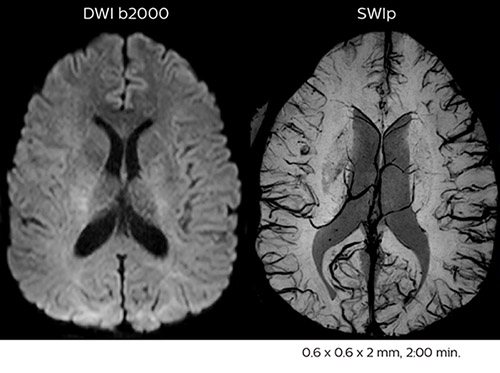

In this example, the optional 3D multishot susceptibility weighted sequence with 0.6 mm isotropic voxels is 2 lesions with a central vein sign (arrows) and one lesion with a phase-rim sign (arrowhead). The total scan time, including SmartBrain and axial PD/T2 3mm, is 11:10 min. and is 18:30 min. with the optional 3D PSIR and 3D SWI multishot included.

“We used to have long examination times for certain types of patients, a few lasting more than 40 minutes,” says Dr. Savatovsky. “What is remarkable, is that now all these examinations are below 30 minutes, which opens up opportunity to add more sequences when needed. It’s really hard to keep a patient for more than 40 minutes in the scanner, but because we have now cut scan times by at least 10 minutes, we can add more sequences without making the exam too long. And this is where the new system helps us make a difference. Examples include our examinations for informing brain tumor classification or giant cell arteritis workup, or for intracranial wall imaging – so in patients where we need several advanced sequences or high resolution sequences.” “We added three additional sequences in our brain neoplasm classification exam: a 3D SWI sequence, APT and ASL on top of 3D morphologic sequences, an isotropic DSC (dynamic susceptibility contrast) and multivoxel spectroscopy. I think that in patients that need a classification for brain mass, for example, we can provide a more detailed and confident diagnosis than before, allowing the clinicians to decide for either a medical workup if no tumor is suspected, or for neurosurgery as soon as possible if a neoplasm is suspected.” “In multiple sclerosis patients, we increasingly include a multishot susceptibility sequence [3] in our routine cases, thanks to the shorter scan times. Our abbreviated MS protocol for brain is around 8 to 9 minutes, so we can ask for one or two additional sequences to visualize the central veins, or to get an additional contrast to better depict posterior fossa lesions. In cases of white matter lesions of unknown significance on FLAIR images, for example when we see high signal hyperintensities in the brain, we can add on more advanced sequences such as PSIR (phase sensitive inversion recovery) or susceptibility-weighted sequences to help us in distinguishing between MS and nonspecific or vascular abnormalities in these inflammatory cases.”

Improved diffusion imaging in stroke patients

Using MultiBand SENSE allowed the staff to improve their diffusion quality. “Our diffusion sequence was already fast before, about 40 seconds. Now with Elition, it still lasts 40 seconds, but we improved the spatial resolution by 0.2 mm and use high b-values to be more sensitive to visualize changes related to acute stroke,” says Dr. Savatovsky. “We now also developed a high resolution DTI sequence (1.3 x 1.3 x 2 mm) that can be reformatted and takes 2 to 5 minutes depending on the coverage. We use it every time we have a doubt, or when we expect the diffusion to be abnormal but don’t see that on the fast sequence. We occasionally spot small ischemic infarctions that would not have been visible with the regular diffusion sequence.”

This is an example of acute ischemic stroke with distal occlusion of the right posterior cerebral artery. Note the improved visibility of the ischemic territory on the diffusion weighted image with high b-value. The 3D FLAIR shows a distal PCA occlusion. The fast SWIp depicts the thrombus on the isolated second echo image. The total scan time (including SmartBrain, preparations and a fast 3D T1w TSE Gd) is 8:00 minutes.

In this patient with acute right motor deficit and aphasia, the b2000 diffusion weighted image is normal. The SWIp image demonstrates more prominent veins in the right hemisphere, which could reflect increased deoxyhemoglobin contents. Fast ASL shows low CBF regions in the left frontal lobe. A follow-up ASL after one hour demonstrates high CBF values in the same area. The final diagnosis was migraine with aura.